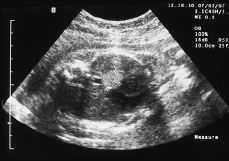

Figura 3.Resonancia magnética intraútero, T2 axial: masa hiperintensa en base pulmonar izquierda.

Este estudio de RM, confirmó la presencia de una masa localizada supradiafragmáticamente en la base del hemitórax izquierdo, situada anterior a la aorta y a la izquierda de la cava. Se trataba de una masa hipointensa en las series potenciadas en T1 e hiperintensa en la serie TSE potenciada en T2 y en la serie TIR, con una intensidad de señal intermedia en Densidad Protónica. No se objetivaron en el seno de la masa o en relación a ella imágenes de vacío de señal que sugirieran la presencia de estructuras vasculares y tampoco se objetivó alteración en la integridad del diafragma ni anomalías cardíacas, pulmonares o abdominales asociadas.